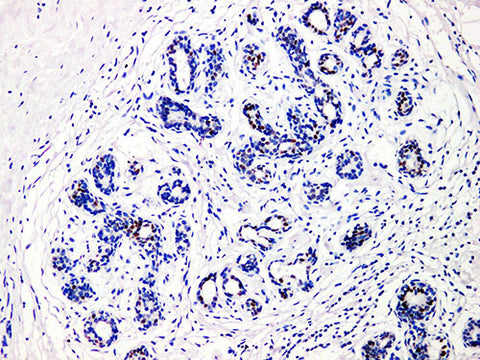

GATA3 Monoclonal Antibody stored at 2~8°C

Applications IHC-P

Tissue Specificity Breast cancer

GATA binding protein 3 (GATA3) is a member of the GATA family of transcription factors (including six members: GATA-1 to GATA-6). It plays an important role in promoting and guiding cell proliferation, development and differentiation in many tissues and cell types. GATA-3 is widely expressed in the epithelial cells of mammary duct glandular cavity and urinary tract epithelium, but not in myoepithelial cells. The expression of GATA-3 is closely associated with the expression of estrogen receptor-α in breast cancer,and there is evidence that GATA-3 can be used to predict the response to hormone therapy in breast cancer patients, and has also been shown to be a new marker for bladder cancer.